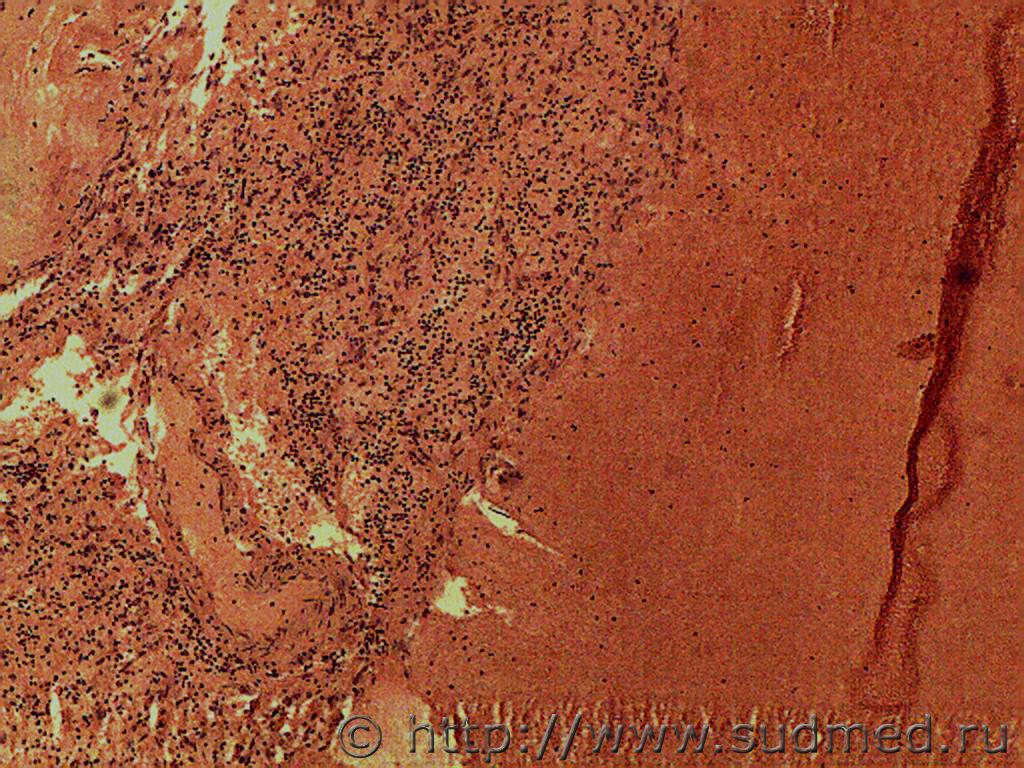

Уважаемые коллеги, пожалуйста, помогите разобраться со скандальным случаем! Из обстоятельств: выпивший мужчина въехал в металлический забор соседей, хозяин забора вытащил мужика из машины и несколько раз ударил по лицу, после чего тот потерял сознание (так в сознание больше и не пришёл). В больнице в приёмнике выставлена кома 2, через 3 дня- кома 3 и смерть. АД 215/141, пульс 160 в мин; об-но: разгибательная реакция на болевые раздражители (хуже справа), фотореакция отсутствует, корнеальные рефлексы вялые, , окулоцефалические рефлексы угнетены. Лицевая мускулатура симметричная. Мышечный тонус- без субъективной разницы сторон, снижены, сухожильные рефлексы с рук торпидные; симптом Бабинского положительный с обеих сторон. Т.к. в больнице сломан аппарат МРТ, выставлен конкурирующий диагноз:1. Ушиб ГМ мезенцефалобульбарная и диэнцефальная форма. 2.Ишемический инсульт в вертебро- базиллярном бассеине. Соп: ИБС, ГБ. В течение 3-х суток состояние ухудшалось, переведён на ИВЛ, смерть. На вскрытии пеломов костей черепа нет, в желудочках 150 мл крови со свёртками. Размягчение вещества мозга в области всех стенок боковых желудочков, мозолистого тела, стволового отдела на глубину от 0,5 до 1,5 см. в зоне размягчения в-во мозга серовато- красноватого цвета с мелкоочаговыми кровоизлияниями; в области дна 3-го желудочка под ММО распространяются кровоизлияния, располагающиеся на основании височных и лобных долей, а также кровоизлияние распространяется под ММО ствола. В веществе ствола мелкоочаговые полосчатые кровоизлияния. Выраженные признаки ГБ, атеросклероз сосудов мозга. Источник кровоизлияния в желудочки не найден. Выкладываю микрофотографии, заранее извиняюсь за качество, т.к. камера плохая. Кратко скажу, что в препаратах ствола САК; ишемия, нейроцитолиз нейронов. Ткань мозга сетчатая, выраженный периваскулярный, перицеллюлярный, периаксональный отек, отёк белого вещества. В препаратах основания правой лобной доли САК, очаговые геморрагии в подкорковых отдела; на одном из препаратов попалась вена с разрывом, стенка её с дегенеративными изменениями, неравномерно истончена со скоплением гомогенных эозинофильных масс, очаговой круглоклеточной инфильтрацией (не знаю как назвать такую патологию, на аневризму, мальформацию не похоже). В подкорковых узлах левого и правого полушарий ткань мозга сетчатая, выраженный периваскулярный, перицеллюлярный, периаксональный отек, отёк белого вещества; местами очень похоже на аксональные шары, но боюсь ошибиться с ДАП, т.к никаких нейроокрасок у нас нет. Родственники трубят тревогу, а я никак не могу закончить экспертизу, мучаюсь, боюсь пропустить травму, не дай Бог, ДАП, хотя склоняюсь к заболеванию, хотя ишемический инфаркт в данном случае тоже сомнителен. По препаратам выраженный атеросклероз сосудов, базиллярная артерия сужена на 40%. Смущает источник кровотечения в желудочки, его на вскрытии не нашли.

Выраженный атеросклероз со степенью сужения базилярной артерии до 40%. Внутримозговые артерии с гиалинозом, периваскулярным скоплением кровяного пигмента.

Микроморфология указывает за ЦВЗ ( атеросклероз,крупных артерии, гиалиноз артериол вещества мозга на фоне генерализванного атеросклероза(т.к.атеросклероз одна из крупных артерии базального отдела м.б.) с признаками гипертониии в виде гиалиноза и склероза артериол и спазма сосудов вещества,гемосидерофаги (нагруженные пигментами макрофаги)- это указывает за периодическое старое кровоизлияние, а разбросанные фибробластно-эндотелиальные клетки для новообразования капилляров и для начало резорбции(т.е. имело место ранние очаги ишемии субстрата мозга), а так же наблюдается дистония сосудов(где сужены и расширены с отмежеванием форменных элементов-именно лейкоцитарное краевое стояние и миграцией единичных лейкоцитов. Нейроцитолиз, клетки тени, умеренный сателлитоз(окружение микроглиальных клеток вокруг нейроцитов), войлочный рисунок местами - за ишемическое размягчение, а кровоизлияние с лейкоцитарной реакцией указывает о давности около 2-3суток. Возможная версия:На фоне ЦВЗ развилось ОНМК и в результате спутанного сознания возможно совершил аварию, удар возможно способствовал дальнейшему развитию ОНМК (если открытых или закрытых ЧМТ исключить по обстоятельству дела). Умеренный алкоголь является неблагополучным фоновым состоянием. Очаговое аксональное повреждение, а не диффузное аксональное повреждение имеет место, как сами указывали на аксональные сфероциты. Но первично ЦВЗ с соответствующими последствиями, а мне кажется вторично травма усугубило состояние.

Для ГБ характерно периферическое сопротивление на уровне артериол, а также патология стенки артериол в виде гиалиноза, склероза именно артериол. А имеющиеся периваскулярные скопления кристалликов гемосидерина в ММО и в веществе периваскулярно с гемосидерофагами, указывает о старом эритродиапедезе при ЦВЗ, а свежие эритроциты вторичные..